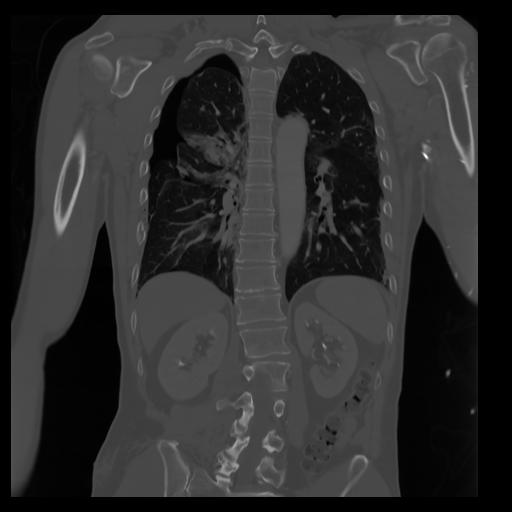

29 CUERPO,CE,Coronal,3.000,CUERPO,Coronal,